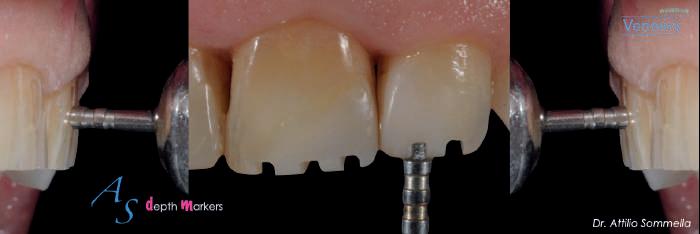

Le statistiche degli ultimi anni hanno evidenziato un aumento esponenziale del numero di trattamenti odontoiatrici mirati al miglioramento dell’estetica del sorriso: sbiancamenti dentali, faccette, protesizzazioni e trattamenti affini, come i filler, sono sempre più richiesti dai pazienti per rendere più armonioso il loro aspetto.

Si è passati, di pari passo, da procedu-

re altamente invasive a terapie sempre meno traumatiche per i pazienti e più predicibili da un punto di vista della prognosi: la possibilità di utilizzare faccette ultrasottili, agenti sbiancanti meno aggressivi e più compatibili con la biologia dello smalto ha reso più fattibili questi trattamenti e più adattabili alle esigenze di ogni singolo paziente. È interessante notare come, da un punto di vista sociale i pazienti però non sono ancora così pronti psicologicamente ad affrontare il classico “ritocchino”, che sia ai denti o al viso o a qualsiasi parte del corpo.

Affiancare ai messaggi di salute quelli relativi al miglioramento dell’estetica dentale poiché, mai come oggi, la terapia deve essere efficace e migliorativa dell’aspetto visivo dei tessuti duri e molli.

Nell’ambito dell’odontoiatria estetica è fondamentale, se non basilare, la collaborazione tra Odontoiatra e Igienista dentale, la collaborazione tra queste due figure professionali deve essere costruttiva e mirata esclusivamente all’interesse del singolo paziente: obietto, il conseguimento del risultato finale che il caso individuale richiede.

L’igienista deve conoscere a fondo i criteri di selezione e di esecuzione di

una terapia di riabilitazione estetica, è l’unico modo per poter stabilire un saldo criterio di selezione dei pazienti e una pianificazione del mantenimento del risultato che conseguirà con l’odontoiatra.

Compito dei professionisti è quello di realizzare una diagnosi del problema, di indicare le procedure più indicate nel caso specifico, capire se è necessario realizzare delle faccette, se il paziente deve sottoporsi ad un trattamento sbiancante, ad una chirurgia mucogengivale o ad una gengivoplastica con laser; oppure indicare un vero e proprio percorso terapeutico che preveda più fasi, sia cosmetiche che protesiche e ortodontiche.

Oggi alcune aziende specializzate nell’ambito dell’estetica dentale hanno cominciato ad organizzare e promuovere corsi specifici in cui la riabilitazione estetica è gestita come una terapia. In questi corsi viene spiegato come un miglioramento estetico non possa pre-

scindere dal ripristino della salute del cavo orale e dal mantenimento della stessa.

Viene affrontato l’intero percorso di un paziente che vuole sottoporsi ad un percorso di miglioramento estetico, le varie fasi “pre” e “post” trattamento, viene evidenziato come qualsiasi ritocco estetico necessiti di un mantenimento nel lungo periodo.

Possiamo quindi concludere che, in questa nuova fase dell’odontoiatria, sia gli Odontoiatri che gli Igienisti dentali devono immergersi in un nuovo modo di pensare e di approcciare il paziente, elevare le proprie conoscenze e approfondire le tecniche relative all’esecuzione delle procedure cliniche. Oggi siamo nel momento storico in cui un cavo orale deve essere in salute clinica e bello da vedere e da mostrare… ma anche duraturo, tenendo ben presente che uno sorriso si riabilita in un tempo definito ma si mantiene per un tempo indefinito.